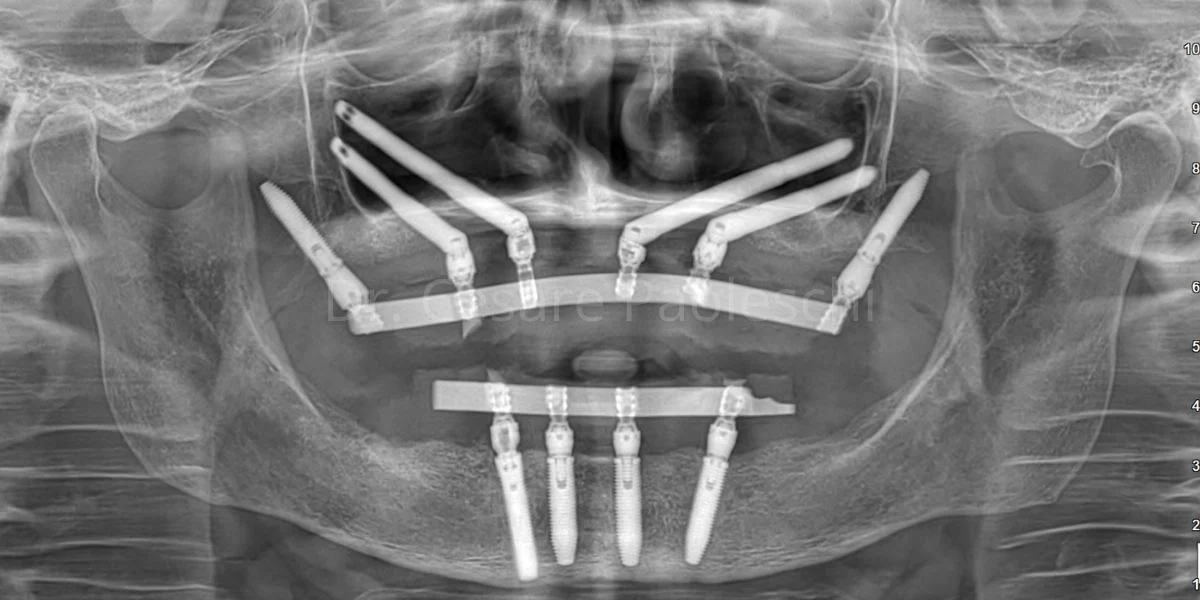

- Posizionamento inclinato nell’osso zigomatico: gli impianti vengono inseriti con un’inclinazione che parte dalla cresta alveolare del mascellare e raggiunge lo zigomo. Questo consente di ottenere una stabilità immediata anche nei casi in cui il mascellare sia completamente atrofico.

- Lunghezza superiore rispetto agli impianti standard: per raggiungere l’osso zigomatico, gli impianti devono attraversare una porzione significativa del viso. Per questo motivo la loro lunghezza varia dai 30 mm fino a oltre 55 mm, contro i 10-18 mm degli impianti tradizionali.

Nella chirurgia implantare zigomatica, l’impianto viene inserito con un’inclinazione precisa attraverso il seno mascellare o in modalità extra-sinusale, fino a raggiungere e fissarsi nell’osso zigomatico. Questo approccio evita la necessità di rigenerare osso e permette, in molti casi, il carico immediato della protesi dentale. - Supporto per protesi fisse